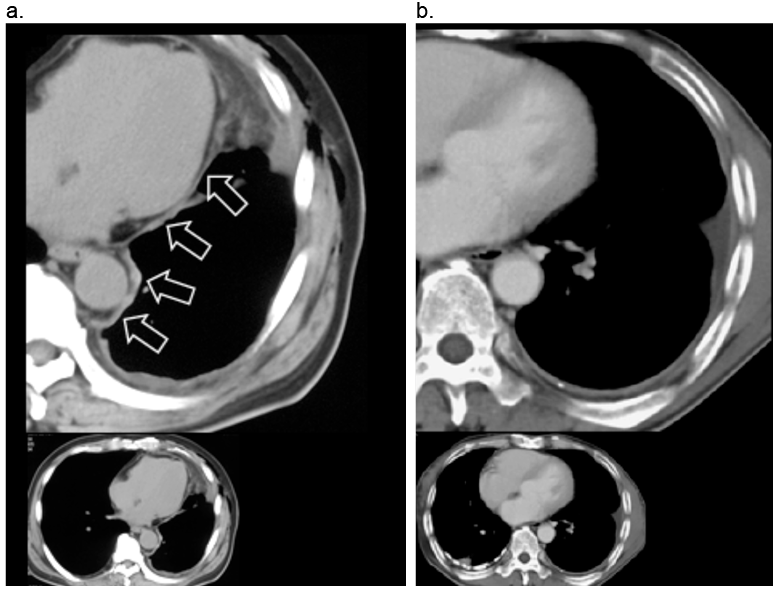

胸膜中皮腫(T4):切除不可能な胸壁浸潤

背部の胸膜腫瘍は、胸膜下脂肪織を超え、肋骨を浸潤し、胸壁に高度に浸潤している(矢印)。